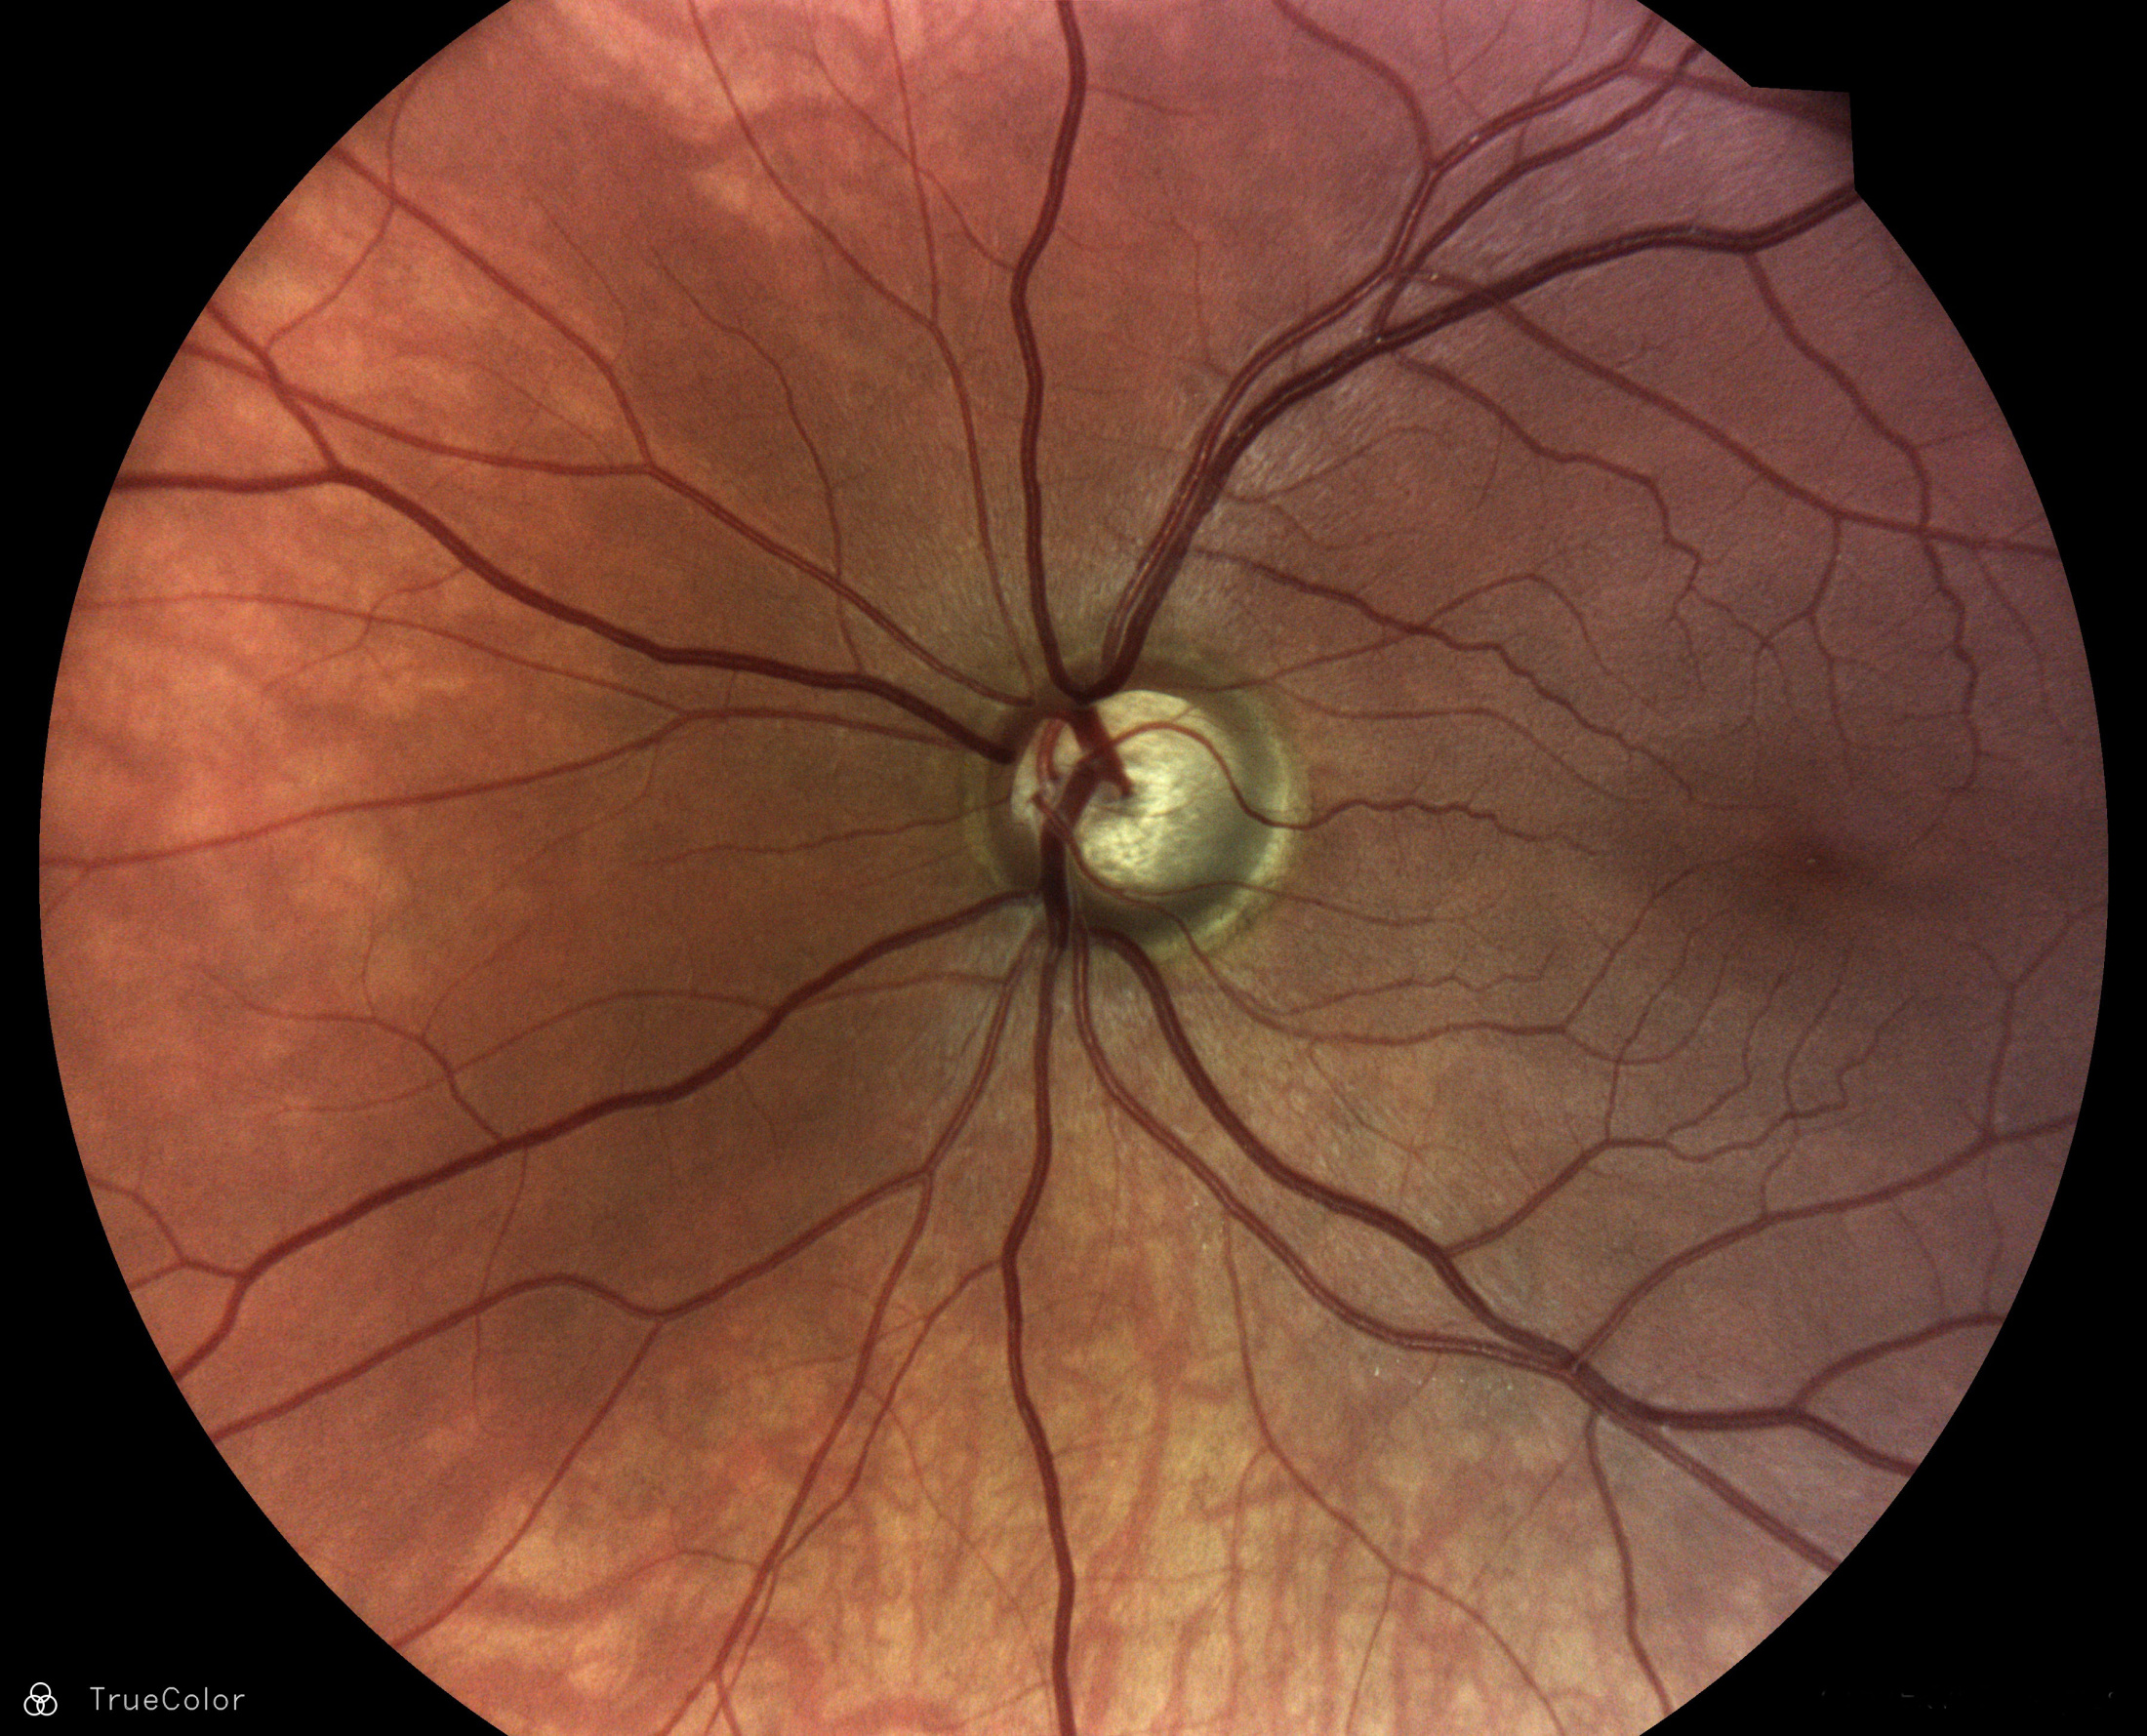

Glaukom - zelený zákal

Zelený zákal alebo glaukom je očná choroba, pri ktorej dochádza k postupnému poškodeniu zrakového nervu. Dlhodobo môže prebiehaž bez povšimnutia, postupne sa objavujú výpadky v zornom poli, alebo ďalšie prejavy. Pri chýbajúcej liečbe hrozí strata zraku. Dôležité je preto chodiť na pravidelné diagnostiky/skríningy a očné kontroly k špecialistom, aby mohol byť prípadný glaukom odhalený, čo najskôr. Aj naša technológia umožnuje praktickým lekárom a špecialistom zo skríningu očného pozadia s vyhodnotením iCare RETCAD® zistiť podorzenie na glaukom.